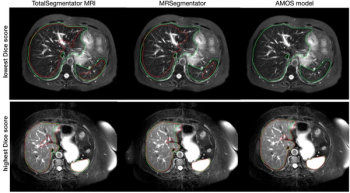

The open-source, deep learning MRI segmentation tool reportedly offers over a 10 percent higher Dice score than similar segmentation models for 40 anatomical structures.